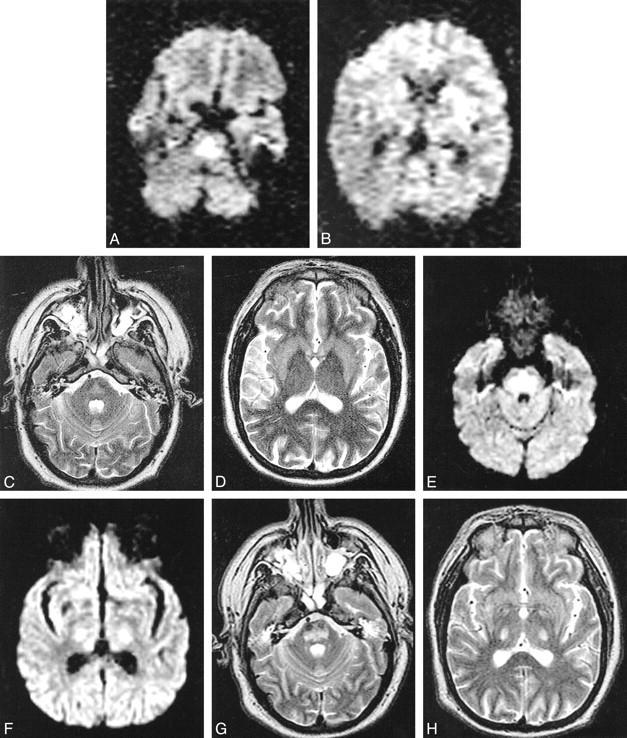

Case 1. MR images obtained using a 1.5-T magnet. Images for study 1 (A–D) were taken in an oblique axial plane 6 days after development of tetraplegia. Images for study 2 (E–H) were taken in an axial plane 21 days after development of tetraplegia.

A, DW image shows increased signal intensity in pons due to restricted water diffusion.

B, DW image is normal in the internal capsules bilaterally.

C and D, In the pons, there is little hyperintensity on the T2-weighted images and low ADC values, with mean ADC in basis pontis being 0.39 ± 0.14 × 10−3 mm2/s (mean ± SD) compared with 0.90 ± 0.15 × 10−3 mm2/s in unaffected white matter.

E, DW image shows increased signal intensity still present in the pons.

F, The DW image shows increased signal intensity present in the internal capsules bilaterally.

G and H, The DW abnormality is accounted for by shine-through from the hyperintense T2-weighted images. Mean ADC in basis pontis (1.09 ± 0.10 × 10−3 mm2/s) is normal compared with that of unaffected white matter (1.05 ± 0.09 × 10−3 mm2/s).

MR images obtained 6 days after developing tetraplegia showed mild T2 hyperintensity restricted to the pons, and DW images showed hyperintensity in the same region (Fig 1A–D). Apparent diffusion coefficient (ADC) maps were derived on a voxel-by-voxel basis using the following formula: [ln (T2 signal) − ln (DWI)]/1000. ADC was decreased in abnormal pontine regions (0.39 ± 0.14 × 10−3 mm2/s; mean ± SD) and was normal in unaffected white matter (0.90 ± 0.15 × 10−3 mm2/s). MR angiography of cervical and intracranial arteries was normal. The patient was transferred to University of Washington Medical Center and on day 21 after tetraplegia, repeat MR imaging (Fig 1E–H) showed areas of hyperintensity on T2-weighted images in the pons, as well as bilateral internal capsules. DW images also showed hyperintensity, but this was due to shine-through of T2 brightness because ADC was now normal in all of these areas. By 10 weeks, the patient's neurologic examination was entirely normal, apart from very mild abnormalities of tone and balance, plus a new intention tremor.